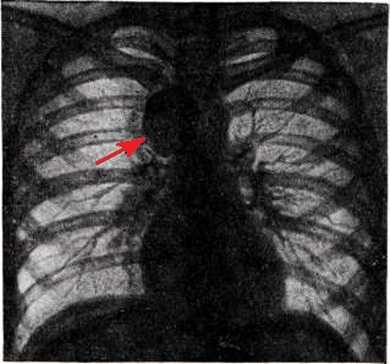

Характерный медленный рост приводит к длительному бессимптомному развитию ганглионевромы и затрудняет ее своевременную диагностику. В некоторых случаях она является случайной находкой при обследовании пациента. Так, при рентгенографии позвоночника или органов грудной клетки ганглионеврома может визуализироваться как примыкающее к позвоночнику однородное затемнение округлой формы. В случае опухоли большого размера может наблюдаться симптом «раздвигания ребер» и появления на них «узур» (вдавлений), обусловленных постоянным давлением опухоли. При озлокачествлении ганглионевромы рентгенологически определяются деструктивные изменения расположенных рядом с ней позвонков и ребер.